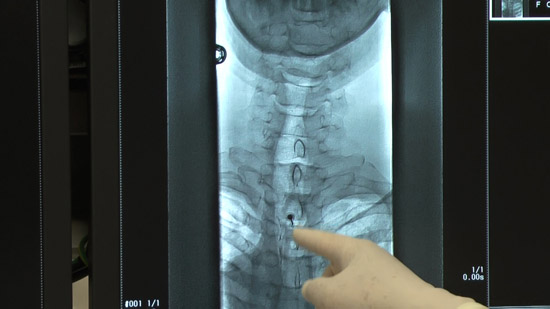

(3)ガイド針(22ゲージ針)を硬膜直前まで挿入

(4)ペンシルポイント穿刺針を硬膜内まで挿入

(5)脳脊髄液の流出を確認